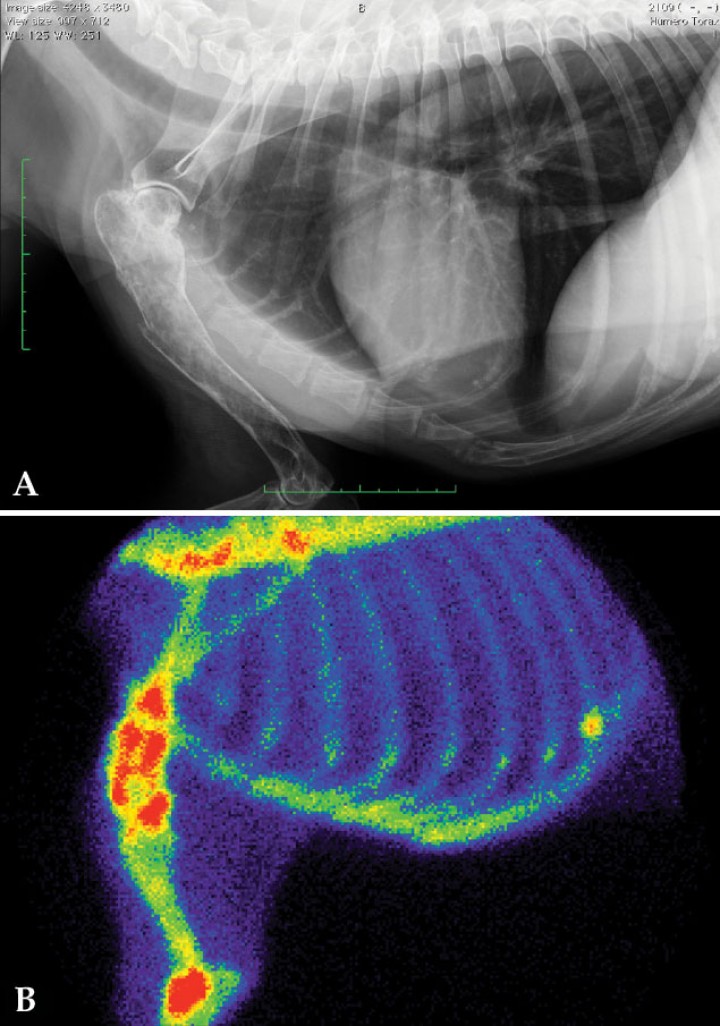

Figura 10

Estudio por imagen de paciente canino con sospecha de tumor óseo primario en húmero derecho. (A) Radiografía con lesión osteolítica en tercio proximal del húmero derecho. (B) Gammagrafía ósea del mismo paciente. Se aprecia un aumento de captación de 99mTc-HDP en el tercio proximal del húmero compatible con neoplasia ósea primaria. Otros hallazgos son el aumento de captación del radiofármaco en la unión costocondral de la costilla n.º 11 (sugerente de artrosis), y en la zona distal de la escápula y articulación del codo (compatibles con enfermedad degenerativa articular).